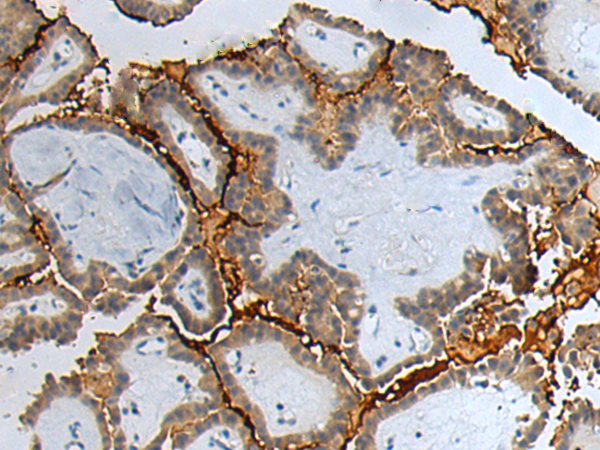

The image is immunohistochemistry of paraffin-embedded Human thyroid cancer tissue using P12656(GTSE1 Antibody) at dilution 1/60. (Original magnification: ×200) |